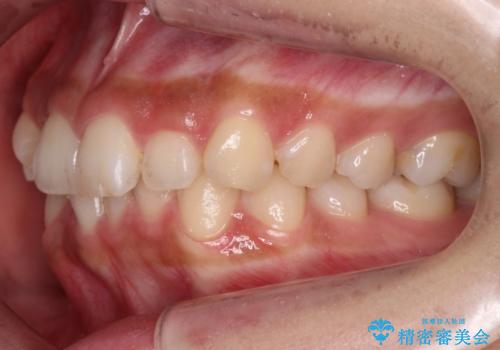

犬歯のねじれ 下の歯のがたがた インビザラインで

- 右上の犬歯のねじれ、下の歯のがたつきを主訴に来院。

インビザラインで歯を抜かずに並べました。

下の前歯のがたがたがそれなりにあったため、リファインメントを行いました。